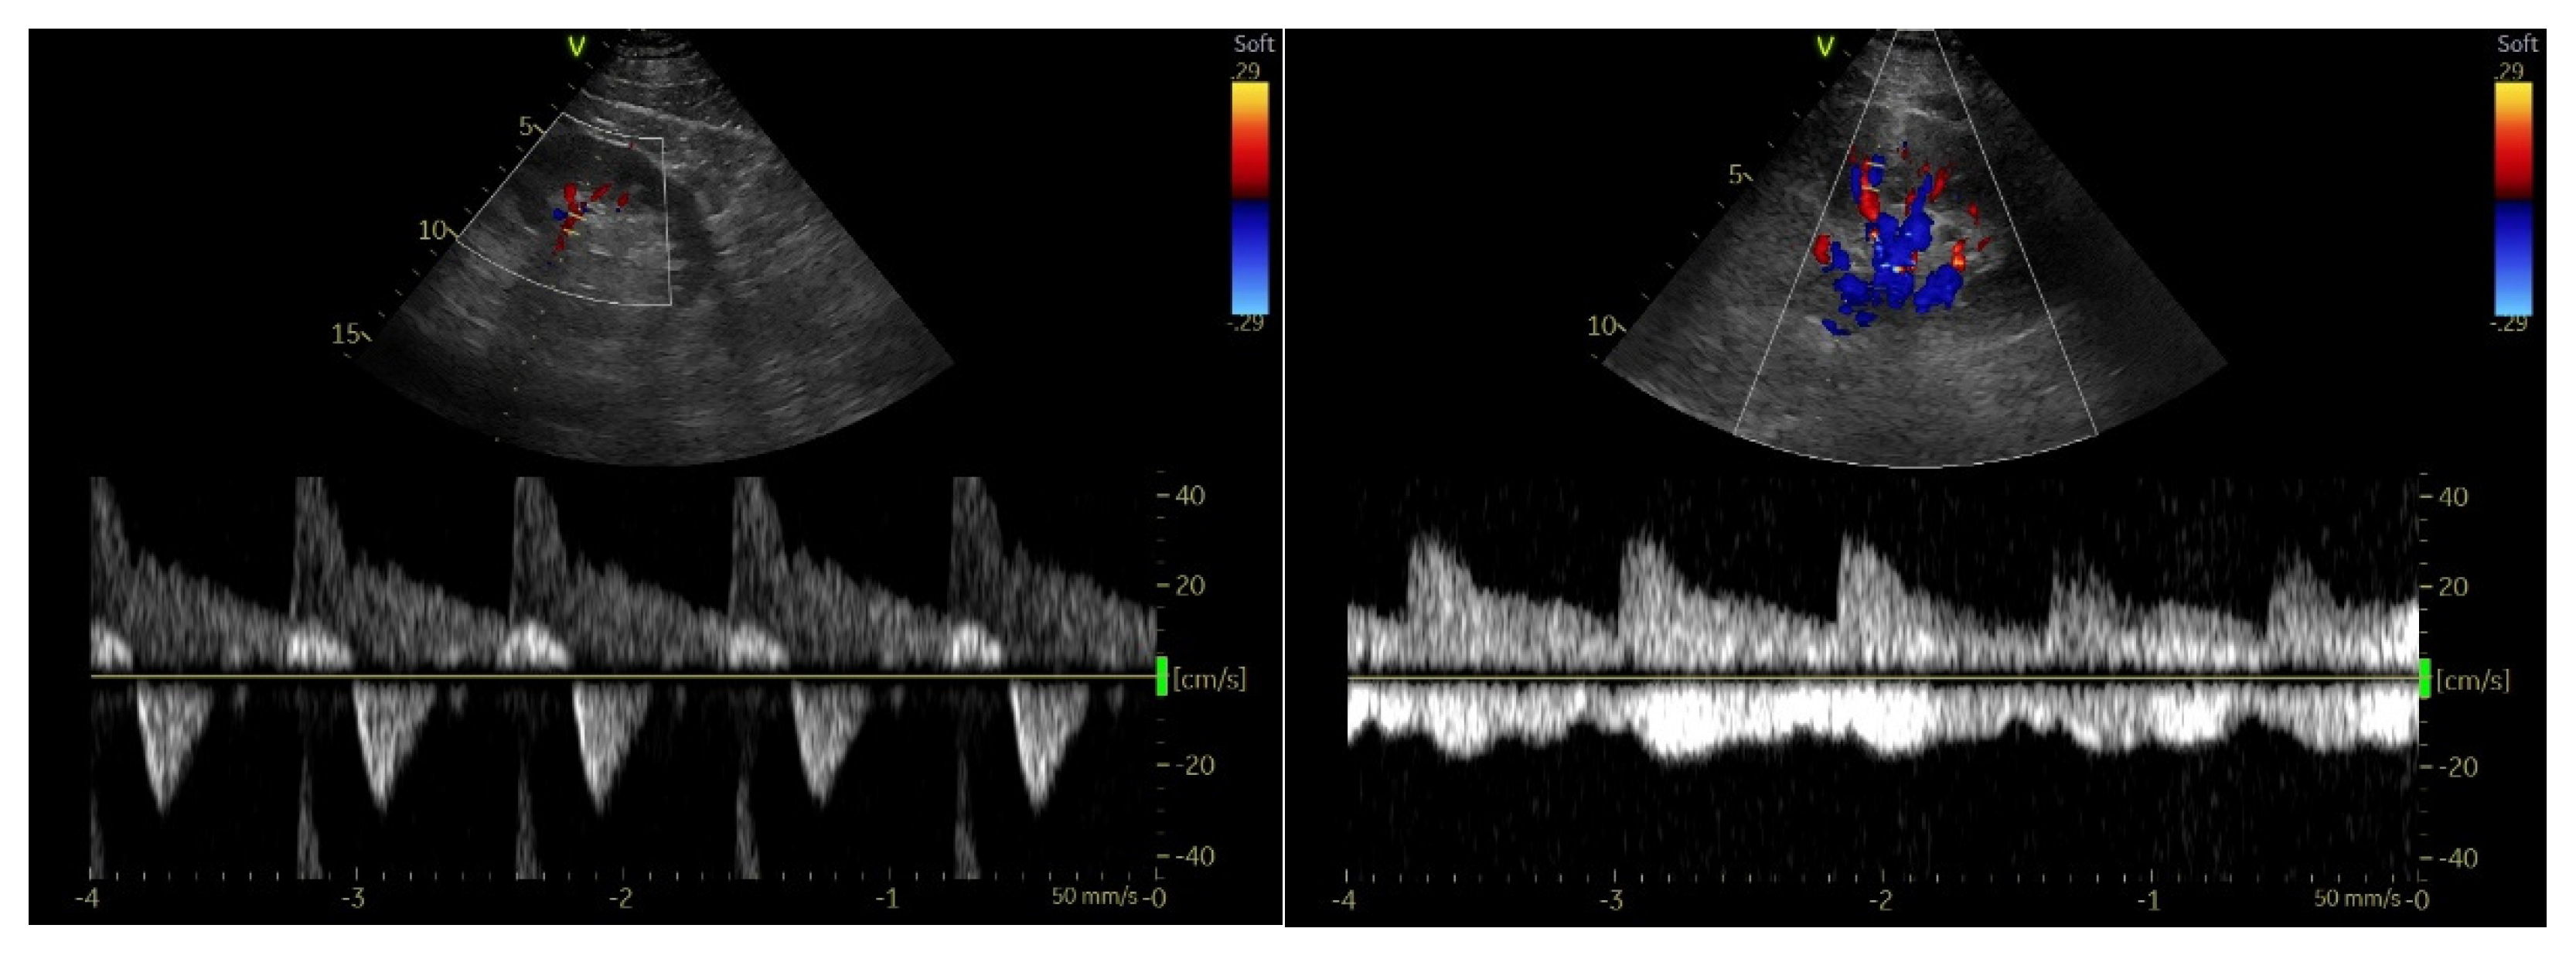

4.2.3. Renal Resistive Index

4.3. Point-of-Care Venous Doppler Ultrasound

4.3.1. Inferior Vena Cava

4.3.2. Hepatic Vein Flow

4.3.3. Portal Vein Flow

4.3.4. Intrarenal Vein Flow